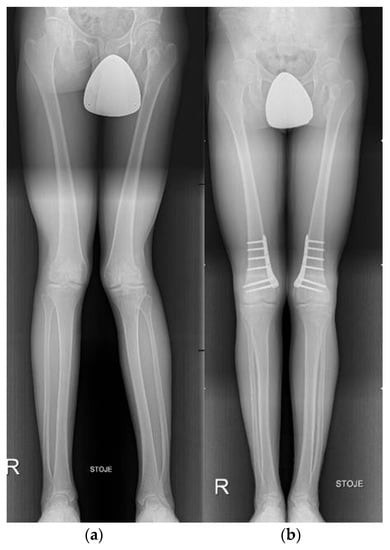

3.6. Knee

- Brumat, P.; Mihalič, R.; Kovač, S.; Trebše, R. Acute Femoral Lengthening in Adults Using Step-Cut Osteotomy, Traction Table, and Proximal Femoral Locking Plate Fixation: Surgical Technique and Report of Three Cases. Indian J. Orthop. 2022, 56, 559–565. [Google Scholar] [CrossRef]

- Wolcott, M.; Traub, S.; Efird, C. High Tibial Osteotomies in the Young Active Patient. Int. Orthop. 2010, 34, 161–166. [Google Scholar] [CrossRef] [PubMed]

- Gomoll, A.H. High Tibial Osteotomy for the Treatment of Unicompartmental Knee Osteoarthritis: A Review of the Literature, Indications, and Technique. Phys. Sportsmed. 2011, 39, 45–54. [Google Scholar] [CrossRef] [PubMed]

- Saragaglia, D.; Sigwalt, L.; Rubens-Duval, B.; Chedal-Bornu, B.; Pailhe, R. Concept of Combined Femoral and Tibial Osteotomies. J. Knee Surg. 2017, 30, 756–763. [Google Scholar] [CrossRef]